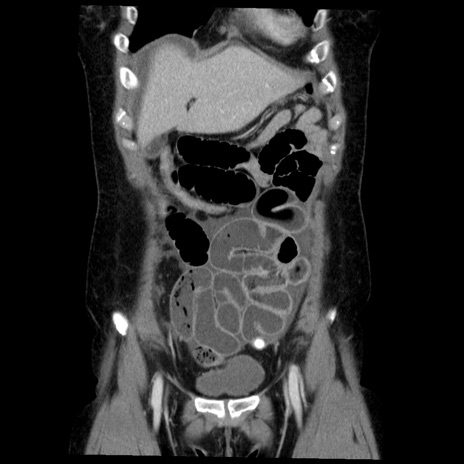

症例6(冠状断像)

【症例】50歳代女性

【主訴】下腹部痛

【現病歴】本日朝より下痢2回あり。 昼食を食べた後、嘔吐3回、下腹部痛認め、症状軽快せず、当院救急搬送。

最終食事:本日昼(生ものなし)。 昨日の夜、刺身を食ぺたとのこと。周囲に同様の症状の者なし。普段、排便は毎日あるとのこと。

【既往歴】卵巣癌術後(8年前に当院で卵巣摘出)

【身体所見】 意識清明、腹部:平坦、腸蠕動音→、やや硬、下腹部自発痛・圧痛あり、反跳痛あり、筋性防御なし。

【データ】WBC 16000、CRP 0.01